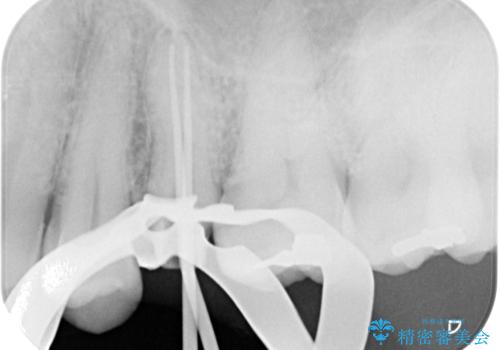

インプラント処置は、抜歯即時埋入を行い、十分な安定性が確認できたため、当日仮歯を装着しました。

インプラントが生着するのを待っている間に反対側の根管治療を行い、左右同時に補綴治療を行いました。